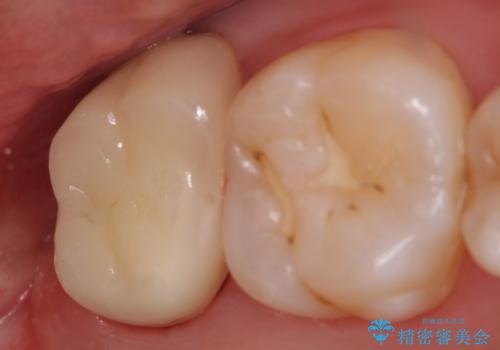

オールセラミッククラウン 鈍痛が続く奥歯の治療

- 他院にて右上7番目の歯の根管治療を行ったが鈍い痛みが治まらないので診て欲しいといらっしゃった方の症例です。

再根管治療を行い症状の消失を確認後、オールセラミッククラウンによる補綴を行いました。

今回用いたオールセラミッククラウンはジルコニアフレームという白い素材の上にセラミックを盛っているため、審美性が非常に高いのが特徴です。

また、ジルコニアは人工ダイヤモンドの材料にも使われているほど高い強度を持っており、そのためオールセラミッククラウンは審美性だけでなく、奥歯やブリッジの補綴も可能とするクラウンです。